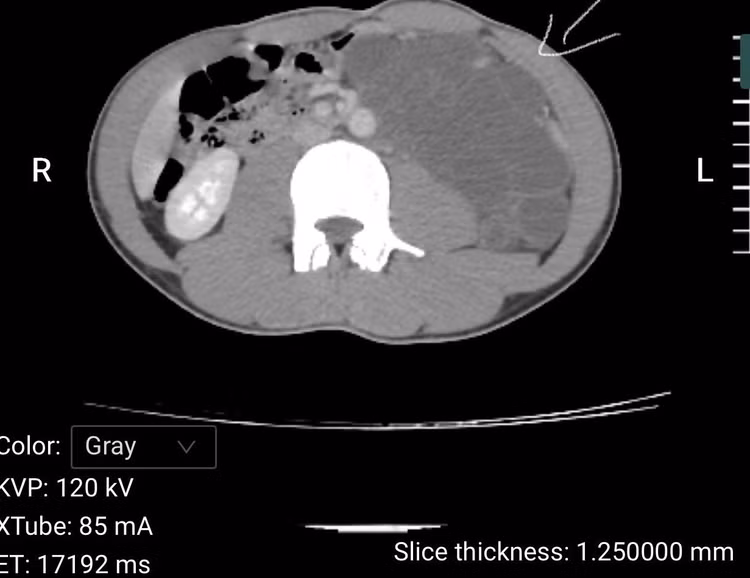

Tại Bệnh viện Đa khoa số 3 tỉnh Lào Cai, sau thăm khám và chụp chiếu, làm các xét nghiệm cận lâm sàng, các bác sĩ chẩn đoán bệnh nhân mắc: U sau phúc mạc bên trái.

Ca mổ được hội chẩn kỹ lưỡng, thực hiện an toàn và thành công, khối u được bóc tách trọn vẹn bảo toàn tối đa các tạng. Sau mổ bệnh nhân hồi phục ổn định.